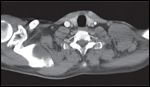

Cerebrospinal fluid (CSF) evaluation was notable for normal glucose, 101 erythrocytes, and 15 leukocytes/mm3 with lymphocytic predominance, and a protein content of 234 mg/dL (normal range, 12–60 mg/dL). CSF lyme polymerase chain reaction was negative. Electrophoretic analysis was suggestive of a monoclonal gammopathy. Serum immunofixation and electrophoresis showed an IgG lambda M-protein, but bone marrow biopsy was normal. Serum antibodies including anti-GQ1b, anti-GD1a, anti-GD1b, anti-GM1, Mycoplasma pneumoniae IgM and IgG, Campylobacter jejunii, Cytomegalovirus (CMV), and Epstein-Barr virus (EBV) IgM were all negative. However, CMV and EBV IgG titers were positive. The anti-Hu antibody titer that had been sent during the initial evaluation, returned positive at > 1:640 by Western Blot. Electromyography (EMG) showed evidence of a mild to moderate, multifocal, mixed but predominantly axonal sensorimotor polyneuropathy. A nerve conduction study (NCS) showed low sensory response amplitudes in the arms with sparing of distal legs consistent with Miller-Fisher syndrome. Chest computerized tomography revealed a large, centrally necrotic mass in the left supraclavicular fossa (Figure 2).

FIGURE 2

Computed Tomography of the Chest With Intravenous Contrast-

Large, centrally necrotic mass extending from the supraclavicular fossa toward the axilla, to the level of the lateral second and third ribs with adjacent adenopathy.